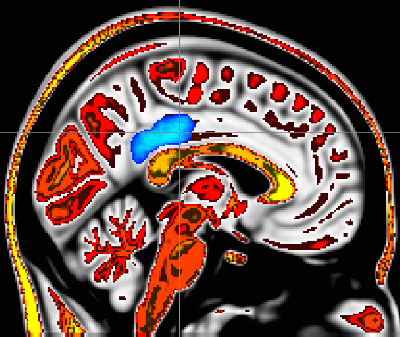

Whole brain analyses revealed that higher dispositional mindfulness during painful heat was associated with greater deactivation of a brain region called the posterior cingulate cortex, a central neural node of the default mode network. Further, in those that reported higher pain, there was greater activation of this critically important brain region.

The default mode network extends from the posterior cingulate cortex to the medial prefrontal cortex of the brain. These two brain regions continuously feed information back and forth. This network is associated with processing feelings of self and mind wandering, Zeidan said.

The study provided novel neurobiological information that showed people with higher mindfulness ratings had less activation in the central nodes (posterior cingulate cortex) of the default network and experienced less pain. Those with lower mindfulness ratings had greater activation of this part of the brain and also felt more pain, Zeidan said.